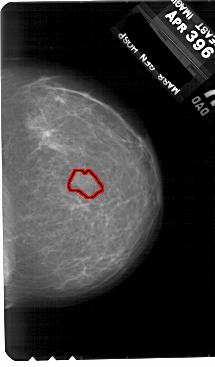

A_1886_1.RIGHT_MLO

RIGHT_MLO LINES 5491 PIXELS_PER_LINE 3451 BITS_PER_PIXEL 12 RESOLUTION 43.5 OVERLAY

FILE: A_1886_1.RIGHT_MLO.OVERLAY

TOTAL_ABNORMALITIES 1

ABNORMALITY 1

LESION_TYPE MASS SHAPE IRREGULAR MARGINS ILL_DEFINED

ASSESSMENT 4

SUBTLETY 3

PATHOLOGY BENIGN

TOTAL_OUTLINES 1

BOUNDARY